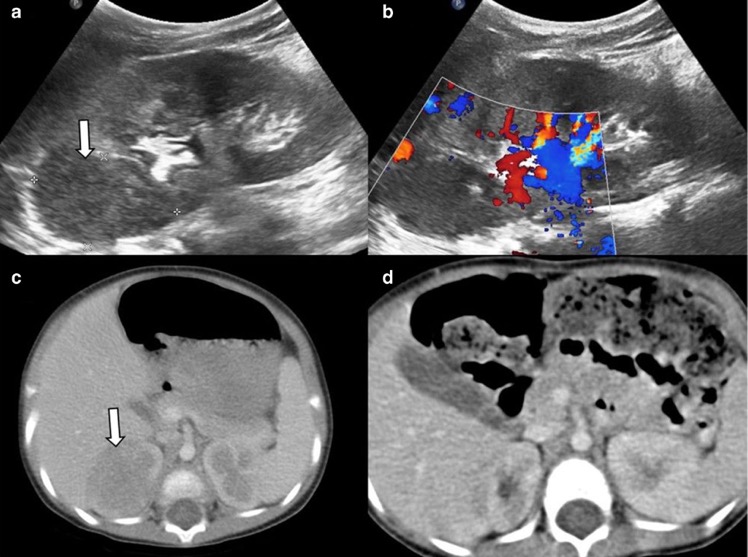

- Pyélonéphrite xanthogranulomateuse